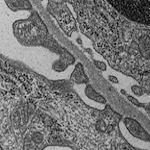

電子顕微鏡サービス

電子顕微鏡観察用の試料作製を相談に応じて代行します。